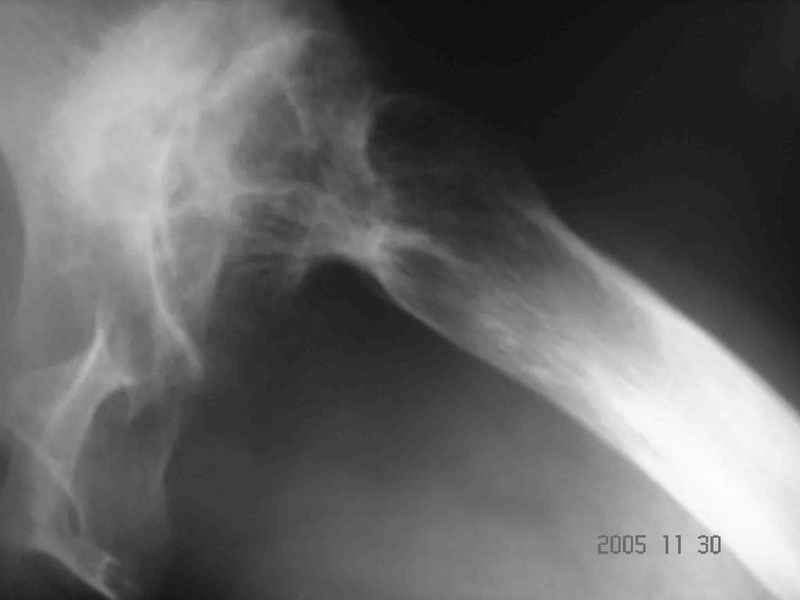

Аксиальный Р-снимок

Вы вполне можете обойтись стандартной клиновидной ножкой, определенные сложности будут в установке вертлужного компонента. Если есть вопросы, не стесняйтесь, спрашивайте.

Аксиальная рентгенограмма подтверждает, что Вы имеете дело со стандартным случаем диспластического коксартроза. Смею присоединиться к мнениям коллег

по поводу бесцементного протезирования сустава. Особого затруднения у опытного специалиста этот случай не вызовет. Возможно протребуется тенотомия

приводящих мышц и некоторый релиз места присоединения ягодичных мышц в области вершины большого вертела. Это позволит одномоментно удлиненить конечность без опасения неврологических осложнений. АИФ.